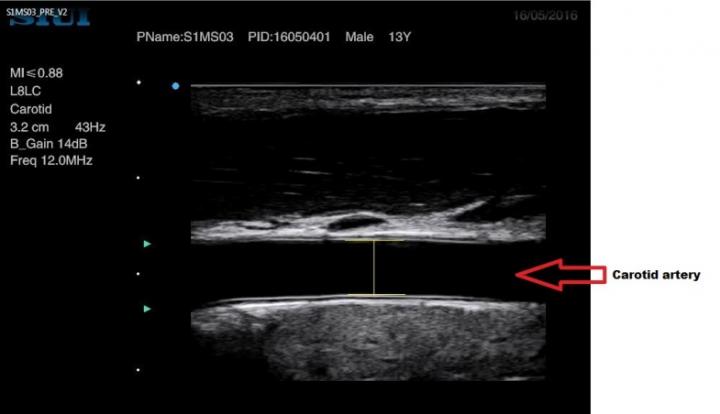

image: Lines in yellow were used to determine arterial diameter and stretching before and following exercise.

This study, conducted by researchers at the Children's Health & Exercise Research Centre, University of Exeter, recruited healthy teenage males (12-15 years old), who underwent testing on four separate occasions across three weeks. In the first visit, participants performed an exercise test to calculate the exercise intensities reflective of vigorous and moderate intensity exercise. After this first visit, all participants completed three experimental conditions in a randomised order and on separate days: 1) vigorous intensity exercise; 2) moderate intensity exercise; and 3) no exercise, which served as a control. Blood pressure was monitored every heart beat before and up to one-hour after the exercise. The measurements also involved ultrasound images of the carotid artery, the main blood vessels that supply the head and neck, to determine the 'stretch' of the artery and how this impacts the control of blood pressure following exercise.